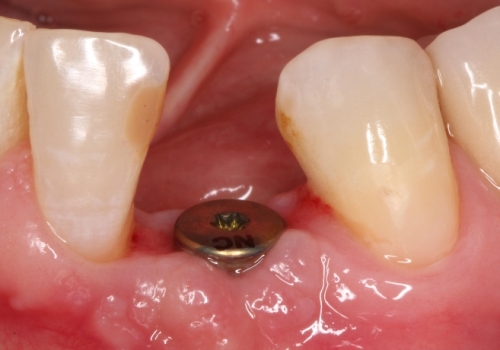

Stomatologiyanın təməl vəzifələrindən biri, itirilmiş dişlərin funksiya və estetik olaraq təbiiyə ən yaxın şəkildə bərpa edə bilməkdir. Dişsizliyin estetik və funksional olaraq yüksək səviyyədə reabilitasiyası, pasiyentlərin çeynəmə, danışma və gülmə kimi funksiyalarını qüsursuz icra edə bilməsi baxımından çox önəmlidir. Diş implantları xüsusi texnologiya hazırlanaraq, itirilmiş dişin bərpası üçün tətbiq edilən süni diş kökləridir. Bu metod təbiiyə ən yaxın bərpanı vəd edən müalicə metodu kimi uzun illərdən bəri beynəlxalq miqyasda geniş tətbiq olunur. İmplantasiya, bu işin peşəkarı yüksək ixtisaslı mütəxəssis tərəfindən qısa bir müddət davam edən prosedur vasitəsilə ağrısız, qısa müddətə və həyati funksiyaların məhdudlaşmaması şərti ilə həyata keçirilən müalicə üsuludur.

Dental implantlar əsasən titandan hazırlanır. Bu materialdan hazırlanmasının ən başlıca səbəbləri, bu metalın orqanizm tərəfindən rədd edilməməsi, heç bir allergik reaksiyaya səbəb olmaması və bu təyinat üçün yetərli möhkəmliyinin olmasıdır. Diş implantları vasitəsilə, tək diş əksikliyindən, çoxsaylı diş əksikliyi və tam dişsizlik halları funksional və estetik bərpa edilə bilir. İmplantın üzərinə hazırlanan diş konstruksiyaları müvafiq vəziyyətlərdə implantların tətbiqi ilə eyni gündə və ya müəyyən bir sağalma dövrünün keçməsindən sonra hazırlana bilir. İmplantların istismar müddəti, doğru planlama və icraat həyata keçirildiyində, eyni zamanda yetərli gigiyenik qulluq şəraitində bir neçə on illik bir periyodu əhatə edə bilir.